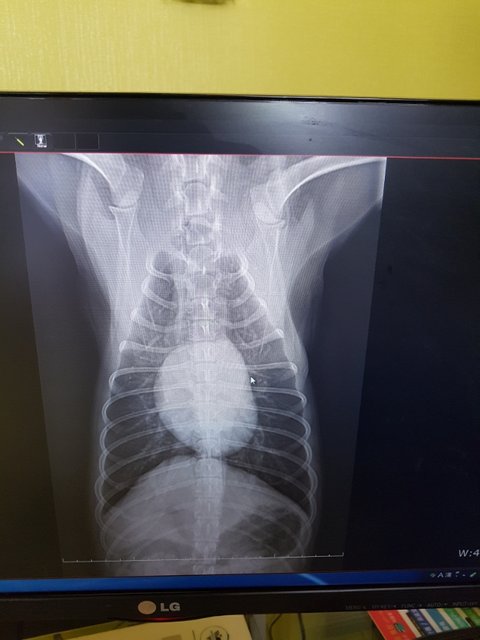

역시나 사상충..

왜 안걸렸겠습니까..

아이모습이 모든걸 말해주는데..